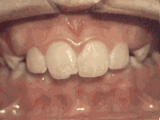

前牙移位,因為有牙齒缺失,導(dǎo)致相鄰牙齒開始沒有秩序的前突,經(jīng)過矯正后是變成這樣的~